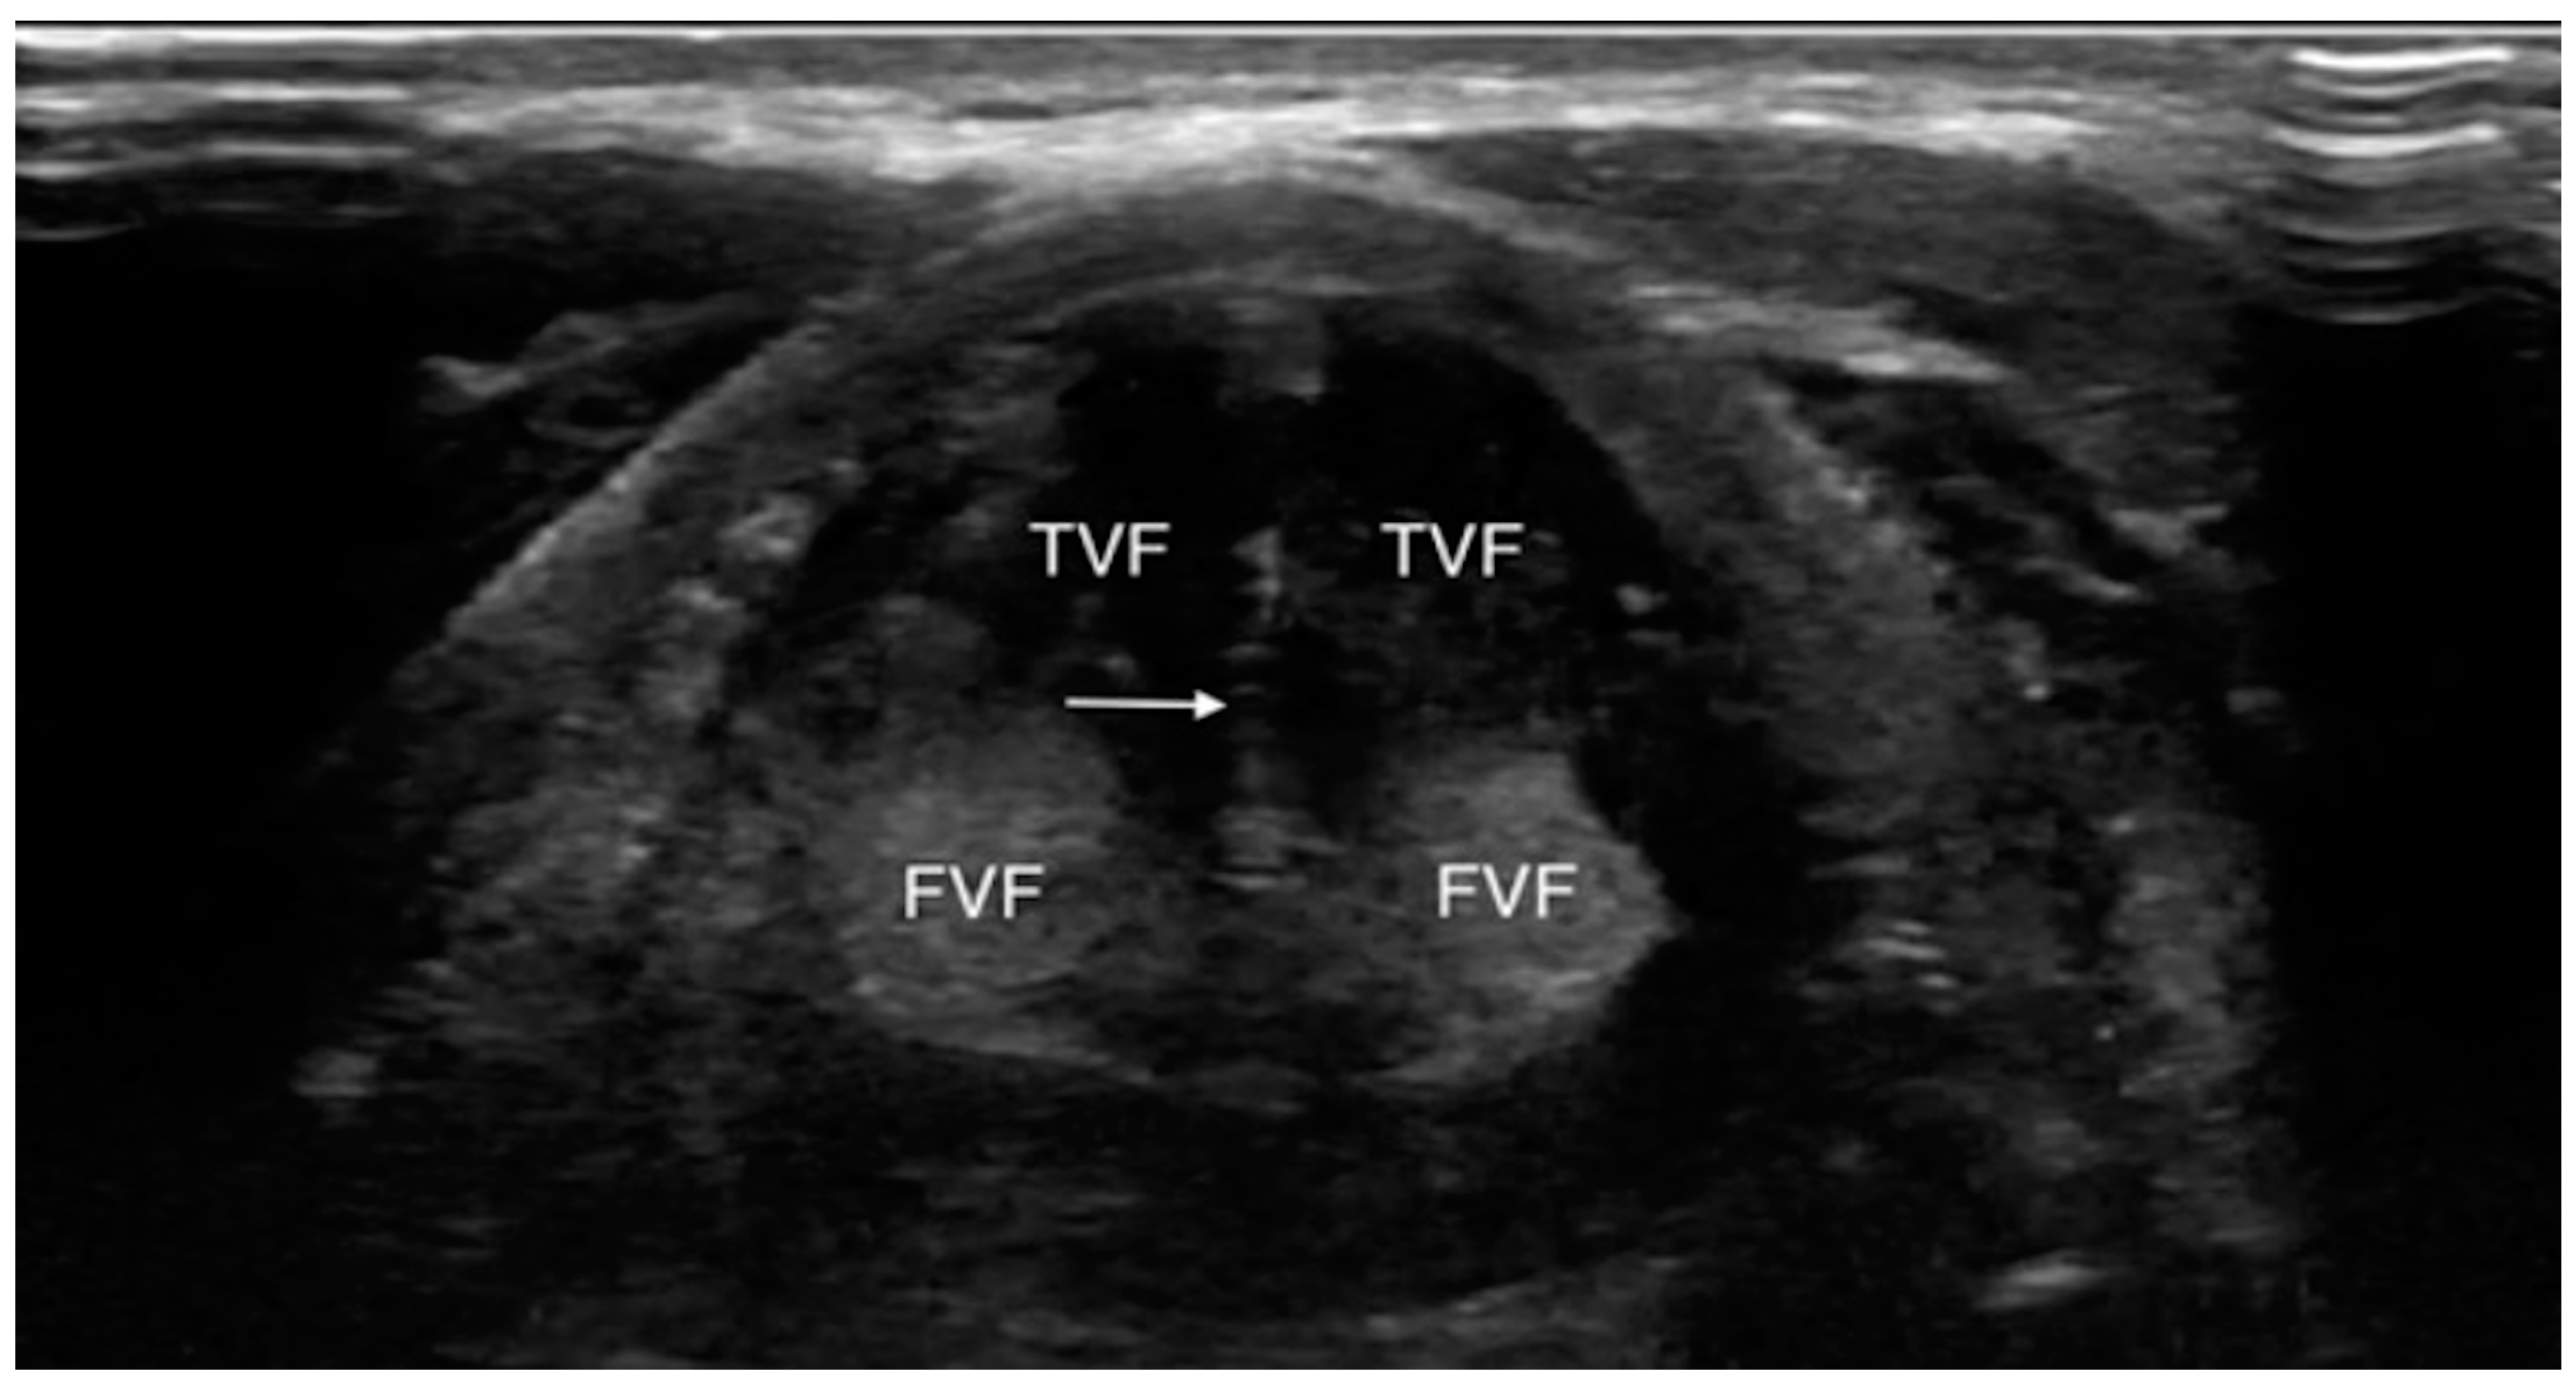

4.1.3. Laryngeal Edema Assessment Pre-Extubation

- Tsai, W.W.; Hung, K.C.; Huang, Y.T.; Yu, C.H.; Lin, C.H.; Chen, I.W.; Sun, C.K. Diagnostic efficacy of sonographic measurement of laryngeal air column width difference for predicting the risk of post-extubation stridor: A meta-analysis of observational studies. Front. Med. 2023, 10, 1109681. [Google Scholar] [CrossRef]